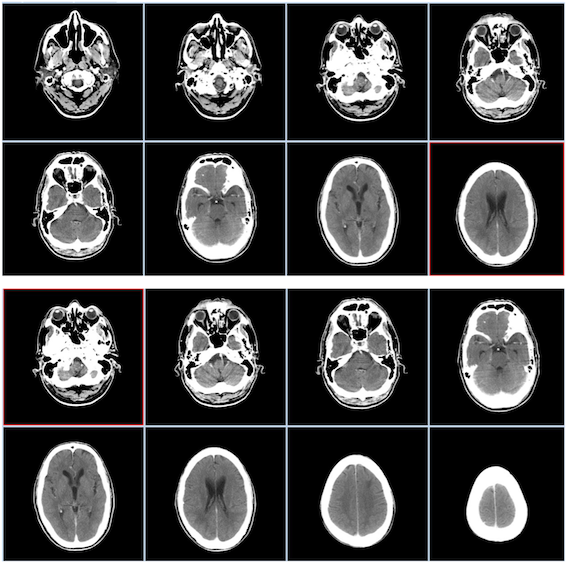

Nejrozsáhlejší studie svého druhu prokázala souvislost mezi výukou hudby a vývojem mozku. Studie zveřejněná v časopise Journal of the American Academy of Child & Adolescent Psychiatry analyzovala snímky mozku 232 dětí ve věku 6-18 let. Vědci objevili důkazy, které naznačují, že hraní hudby mění oblasti mozku regulující chování a motoriku.

Předchozí studie prokázaly souvislost mezi ztlušťováním a ztenčováním určitých oblastí mozkové kůry a psychickými problémy u dětí, jako jsou úzkost, deprese a problémy s poruchami pozornosti.

V tomto novém výzkumu bylo zjištěno, že výuka hudby ovlivňuje tloušťku oblasti mozkové kůry spojené s "exekutivními funkcemi, včetně pracovní paměti, kontroly pozornosti a také organizace a plánování budoucnosti". Jinými slovy, cílená a kvalitní výuka hry na hudební nástroj podporují paměťové procesy, zlepšují pozornost a schopnost plánovat.